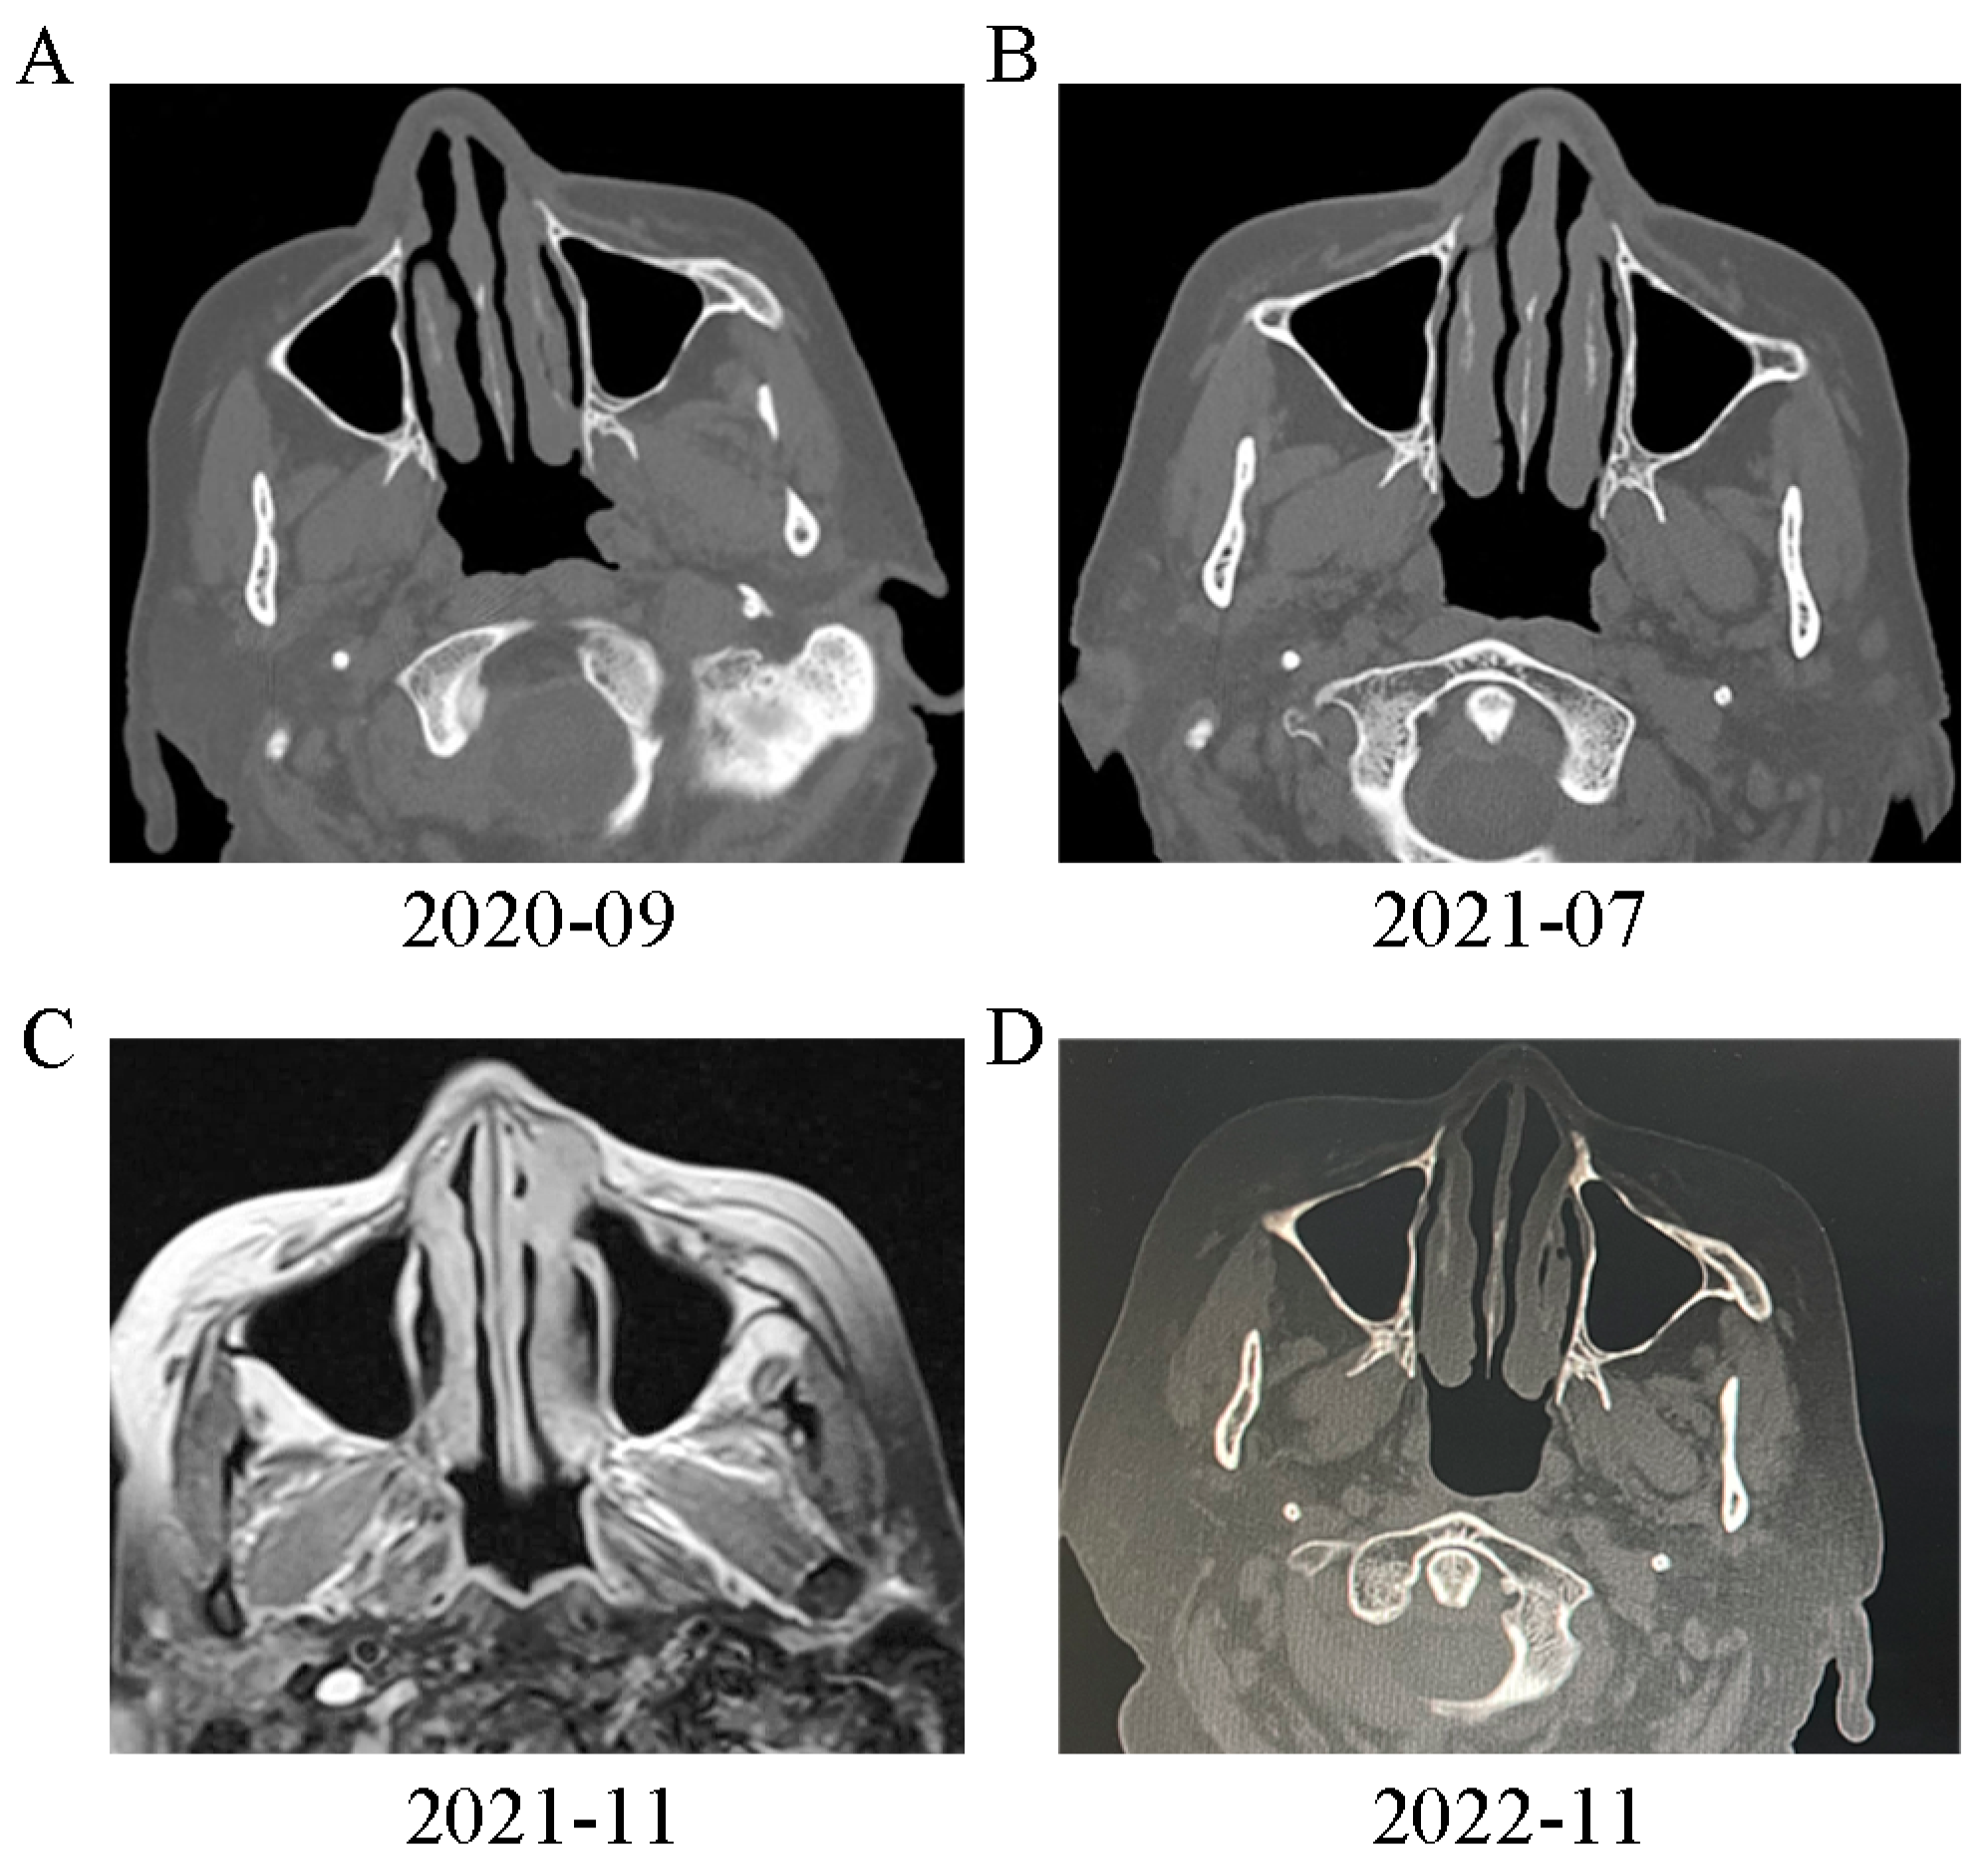

We also observed that the patient also had a series of extrapulmonary abnormalities. First, the patient’s right middle finger became slightly swollen in 2015, although she did not seek medical advice at this time. In April 2019, the patient felt pain and experienced an exacerbation of swelling in her right middle finger; furthermore, some soft tissue nodules also appeared in her right arm. Digital X-ray examination of the right hand indicated ground glass opacity in the bone marrow cavity and destruction of the bone cortex (Figure 2A). The patient underwent curettage and bone grafting of the proximal phalanx of the right middle finger. A soft jelly-like substance was removed and pathological analysis suggested granulomas with infiltration of lymphocytes and plasma cells without caseous necrosis (Figure 3A). A digital X-ray examination was performed after surgery (Figure 2B), and the symptoms of the right hand were partially relieved. In 2021, the patient’s right middle finger became swollen and painful again (Figure 2D); digital X-ray examination indicated hyperplastic and pathological fracture-like manifestations in the proximal phalanx of the right middle finger (Figure 2C). Considering the possibility of malignant lesions, the patient’s finger was amputated (Figure 2E); pathological analysis of the right middle finger and right arm tissue indicated chronic inflammatory granulomas without caseous necrosis (Figure 3B). In addition, the patient had been diagnosed with ocular tuberculosis 50 years earlier and had been treated by isoniazid. She was diagnosed with binocular angle-closure glaucoma and age-related cataract in November 2020. Subsequently, the patient suffered from nasal obstructive for two years, and underwent sinonasal CT examination in September 2020; this revealed irregularities in the left sinonasal bone with multiple low-density areas and local swollen soft tissues (Figure 4A). The patient did not receive any treatment for this. The nasal obstruction became aggravated, and the tissues around the nose gradually became swollen. A sinonasal CT in July 2021 indicated enlargement of the destruction area in sinonasal bone with both sides affected (Figure 4B). Sinonasal magnetic resonance imaging in November 2021 indicated local narrowing of the left nasal meatus in addition to the other manifestations noted previously (Figure 4C).

Figure 4.

(A) Sinonasal CT in 7 September 2020 revealed irregularities in the left sinonasal bone with multiple low-density areas and the local swollen soft tissues. (B) The sinonasal CT in 29 July 2021 indicated enlargement of the destruction area in sinonasal bone with both sides affected. (C) Sinonasal magnetic resonance imaging in 5 November 2021 indicated local narrowing of the left nasal meatus in addition to the above manifestations. (D) After prednisone treatment for 3 months, sinonasal CT was performed and indicated significant improvement of destruction in the sinonasal bone.

Differential diagnosis was mainly focused on granulomatous diseases, which could be primary divided into infectious ones and non-infectious ones according to the etiology. For infectious granulomatous diseases, tuberculosis and fungal infections are the most common causes. The pure protein derivatives (PPD) and T-SPOT test was negative (Table 1), and anti-acid staining of biopsies was also negative; this could exclude the possibility of tuberculosis. The Glucatell test, glactomannan test and cryptococcus antigen test were also performed; these were all negative (Table 1). Thus, the possibility of fungal infection was very low. Non-infectious granulomatous diseases include sarcoidosis, hypersensitivity pneumonia, vasculitis, connective tissue disease (CTD) and related diseases. The patient had no CTD-related symptoms or allergen exposure experience, and her CTD-related antibodies were all negative (Table 1). Granulomatous vasculitis (eosinophilic granulomatosis with polyangiitis (EGPA) and granulomatosis with polyangiitis (GPA)) may lead to manifestations like our patient in the case. Our patient only has sinusitis and lung infiltration imaging, which do not support the diagnosis of EGPA. The negative anti-neutrophil cytoplasmic antibodies, normal urinalysis (Table 1) and the lack of necrosis in granulomas exclude the possibility of GPA in our patient. The IgG4 staining of biopsies was also negative. Considering the systematic granuloma manifestations and elevated CD4+/CD8+ T cells in BAL fluid, the patient was finally diagnosed with sarcoidosis. The patient was suggested to start oral corticosteroid therapy, but she temporarily refused the therapy due to adverse reactions. In August 2022, the patient received prednisone treatment at a dose of 30 mg per day due to the exacerbation of breath shortness. The dose of corticosteroid was tapered by 5 mg/day every month (30 mg/day for the first month, 25 mg/day for the second month and 20 mg/day for the third month). After prednisone treatment for 3 months, the breath shortness was largely ameliorated, and the sinonasal CT indicated significant improvement of destruction in the sinonasal bone (Figure 4D). To present the patient’s symptoms and signs better, Figure 5 summarizes the patient’s manifestations in a chronological order.